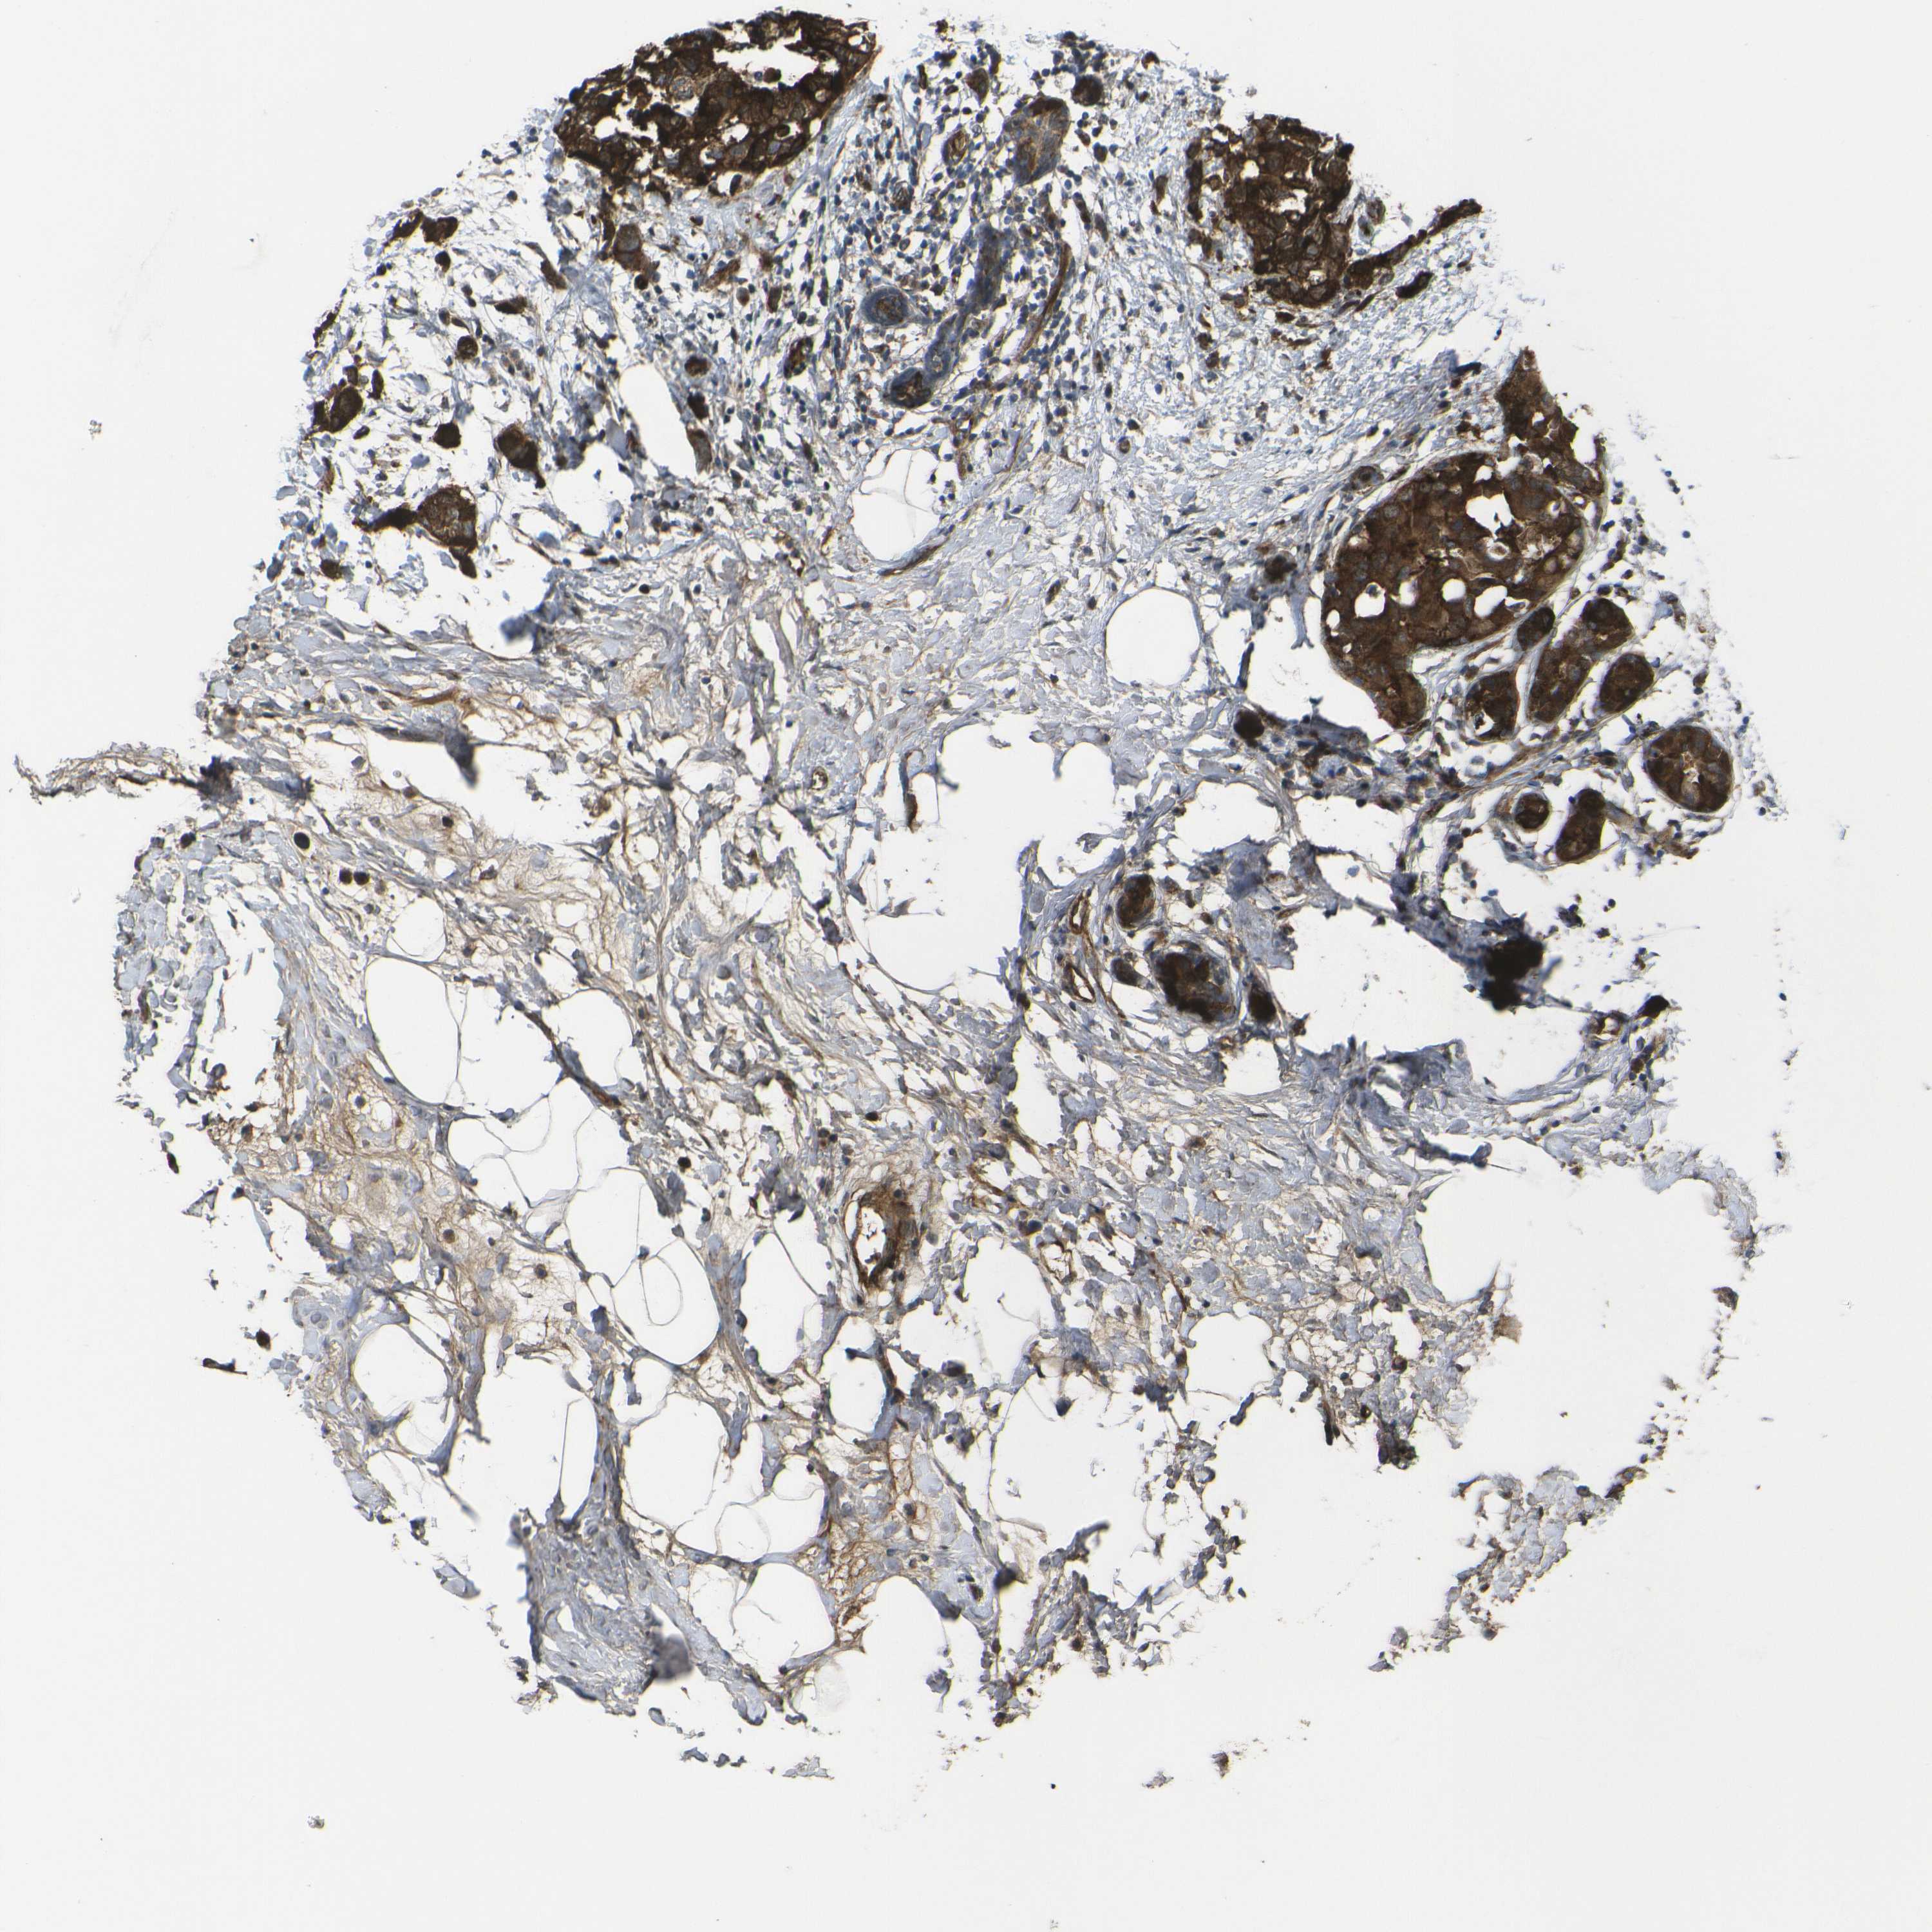

BRCA TCGA BRCA VALIDATION PROTEIN EXPRESSION

ANTIBODIES

AND

VALIDATION